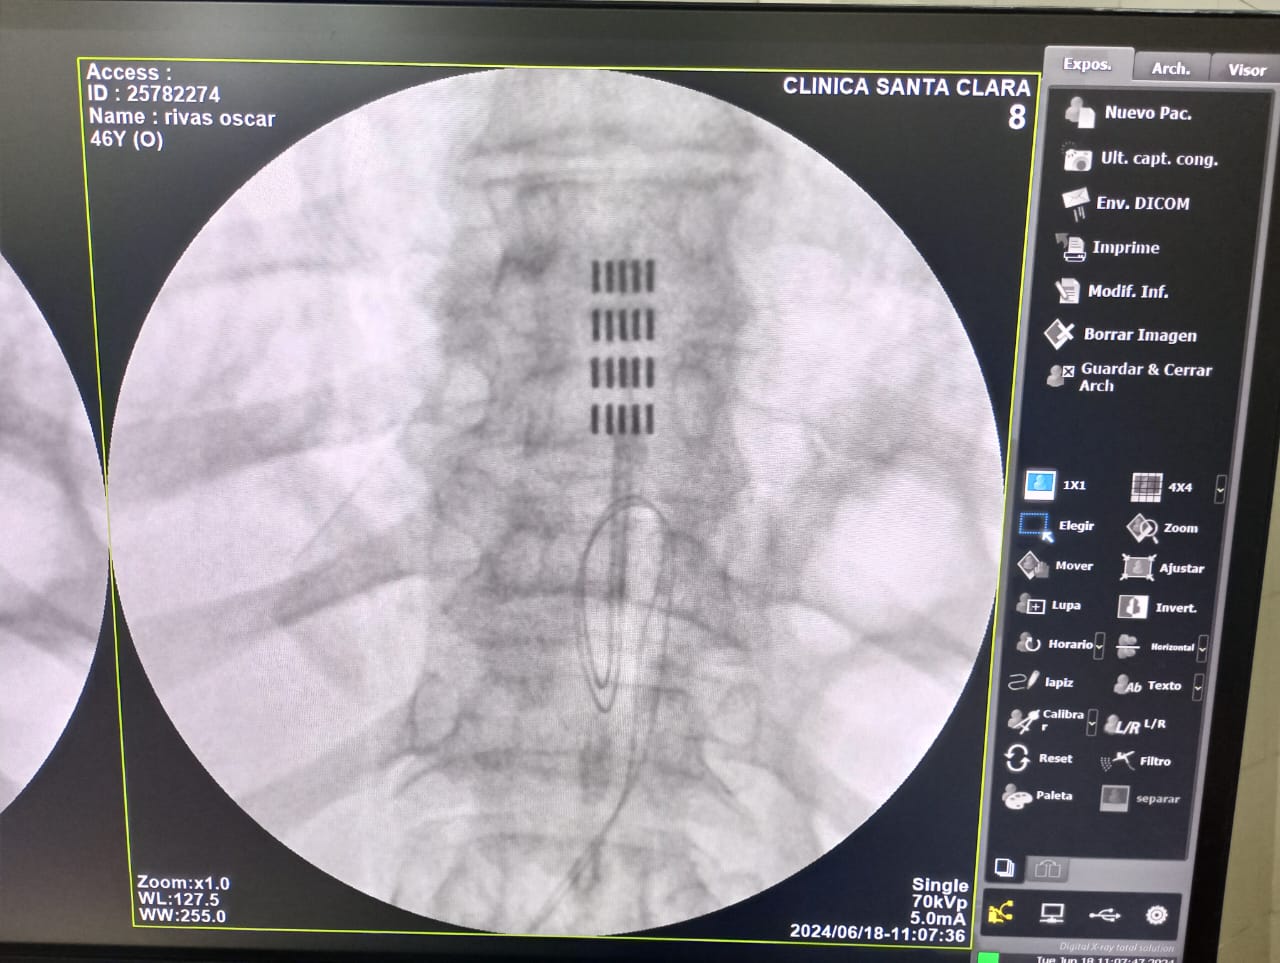

Como neurocirujano funcional especializado en cirugía del dolor mediante estimulación medular (SCS), veo cada día cómo la tecnología puede transformar vidas. La neuromodulación no es ciencia ficción: es una herramienta concreta para pacientes con dolor crónico refractario que han agotado otras opciones.